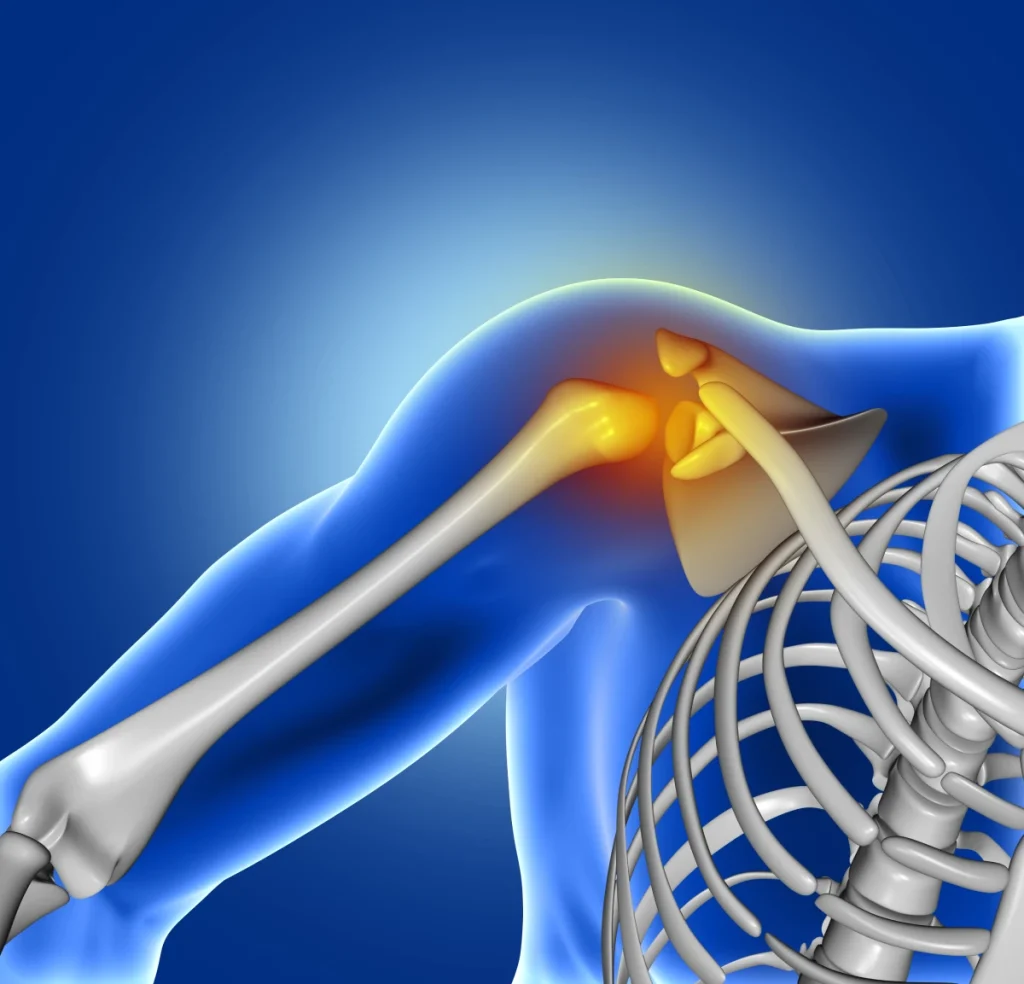

Prótesis de hombro

Los problemas degenerativos del hombro son una de las principales causas de incapacidad laboral. Para los pacientes supone un problema de salud equiparable, en su percepción de enfermedad, a la insuficiencia cardíaca o la diabetes, por ejemplo.

Actualmente la prótesis de hombro, que podría ser una solución para muchos enfermos, es desconocida para gran parte de la población.

La prótesis de hombro, artroplastia de hombro o sustitución protésica de hombro es un procedimiento quirúrgico mediante el cual se sustituye la articulación glenohumeral (la articulación entre la cabeza del húmero y la escápula) por un implante protésico. Este procedimiento está indicado fundamentalmente en casos de artrosis evolucionada o de artritis severa de hombro (como en la artritis reumatoide) para controlar el dolor y recuperar la funcionalidad perdida; y también tras algunas fracturas de hombro proximal en las que la reconstrucción quirúrgica no es posible, por la más que posible no viabilidad en la consolidación de las fracturas existentes.

Existen fundamentalmente dos modalidades de prótesis de hombro: Prótesis anatómica o prótesis invertida. El tipo de cirugía va a depender fundamentalmente del daño que tengan las estructuras tendinosas adyacentes que sirven de soporte a la articulación.

La prótesis anatómica de hombro reproduce la anatomía natural del hombro. Para su correcto funcionamiento requiere que el aparato tendinoso del hombro esté conservado.

En la prótesis invertida de hombro el húmero se excava para que aloje y se articule sobre el componente escapular, en este caso semiesférico, al revés de la disposición natural de la articulación. La sustitución inversa permite utilizar el músculo deltoides para reforzar la articulación, añadiendo estabilidad y mejorando los resultados funcionales.

Esto es muy útil en pacientes que tienen dañados el manguito de los rotadores y los tendones del hombro. Algunos de estos pacientes llegan a tener una grave alteración funcional llamada “hombro pseudoparalítico”, en que no pueden apenas mover el brazo; para esta situación no existían tratamientos exitosos hasta la aparición de las prótesis invertidas; ahora gracias a ellas los pacientes pueden recuperar una función adecuada en la mayor parte de los casos.

La prótesis de hombro se coloca mediante cirugía, bajo anestesia general. La operación dura unos 90-120 minutos y el paciente permanece ingresado, habitualmente, de 4 a 7 días tras la intervención.

Poco tiempo después de la cirugía se le enseñan al paciente una serie de ejercicios suaves de movilización pasiva. Sin embargo la rehabilitación propiamente dicha no comienza hasta 4semanas tras la operación.